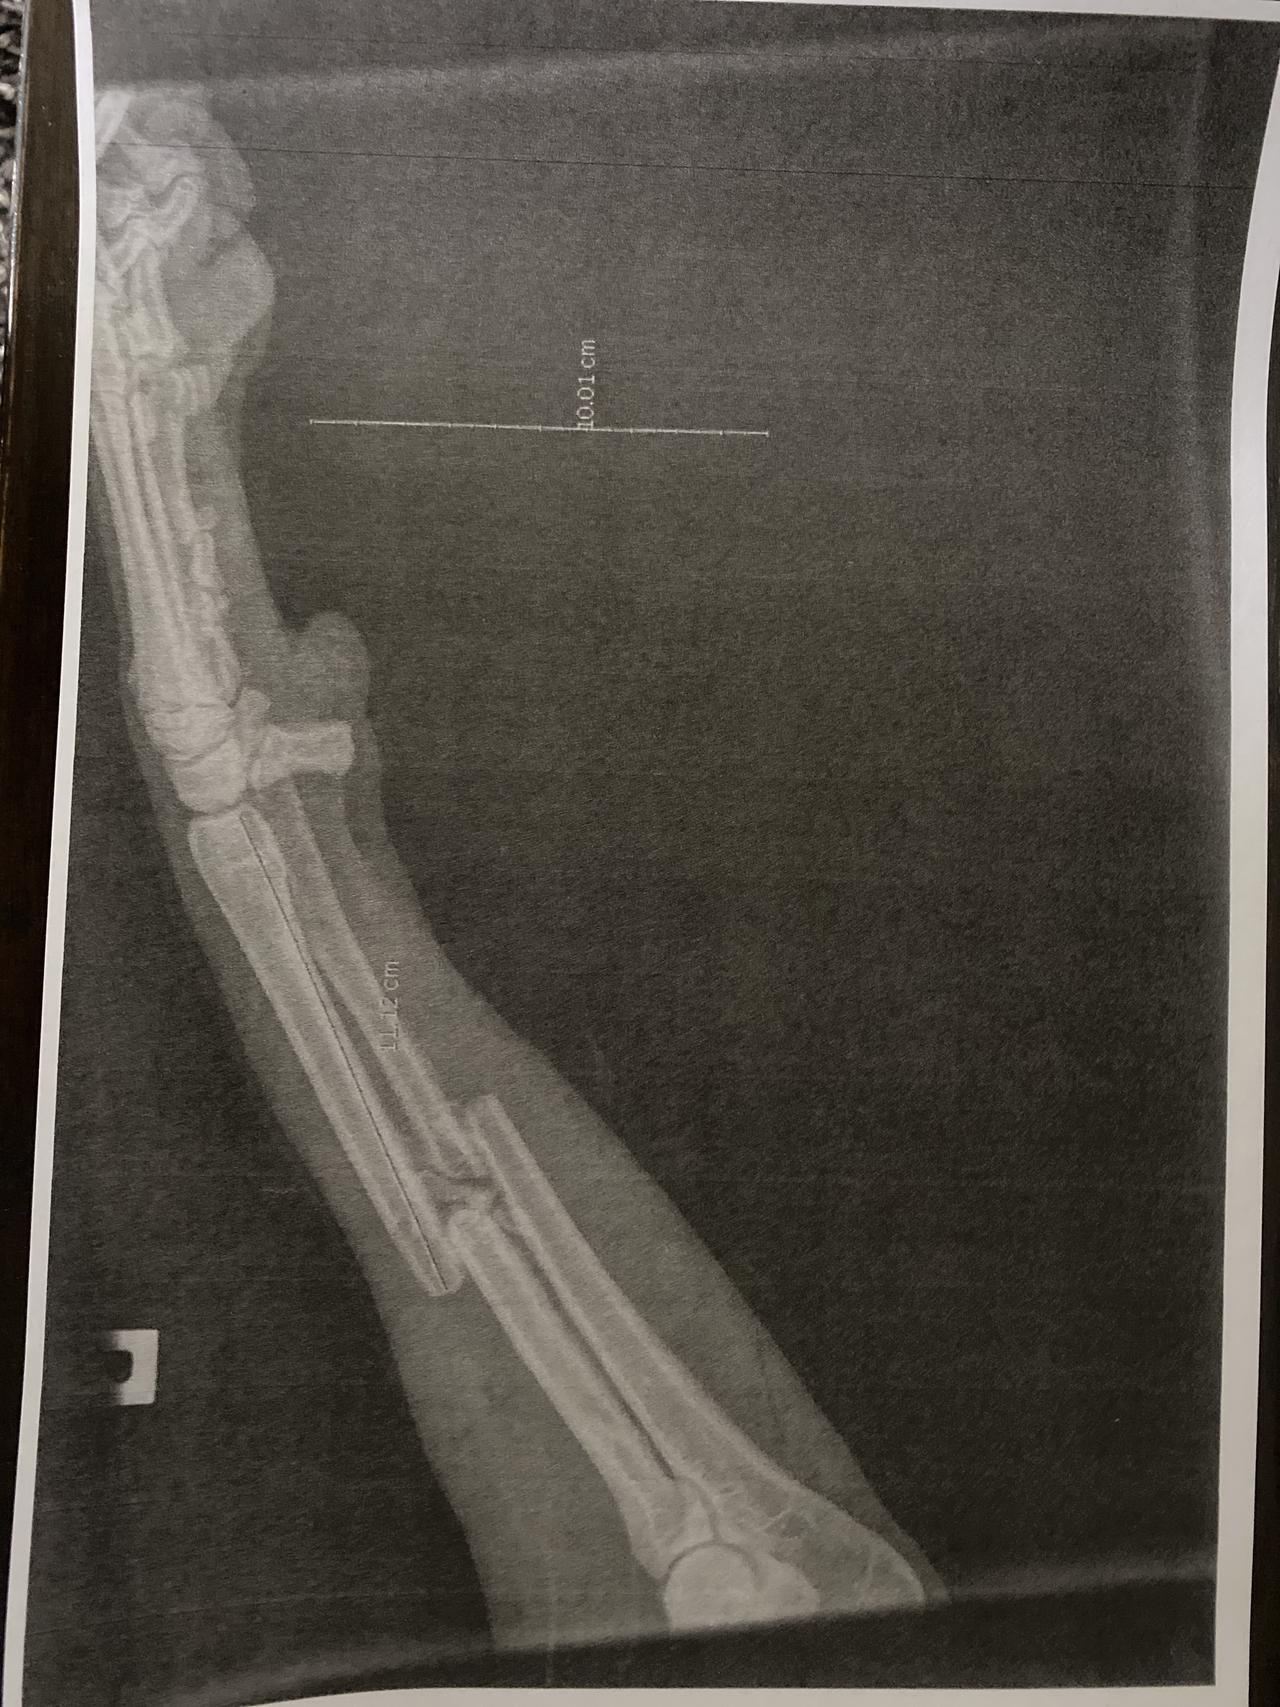

• X-ray post surgery

Post surgery

Delta is doing well but is still in quite alot of pain. She is going out for very short lead walks and while these were supposed to be getting a bit longer we have had to keep them short as she is struggling. She had her first physio session this week and we now have lots of stretches, exercises and massage to do to help her recover. She has a follow up xray on the 1st October which will tell us if the surgery was a success. She may need further surgery to remove the pins and plate once the leg is healed or worst case scenario lose her leg.